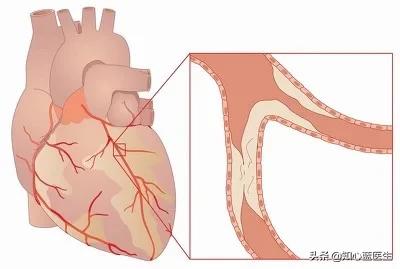

でもね。もし冠動脈の内腔が狭くなっていれば、心筋の酸素需要が増大しても、冠動脈の血液供給はそれに応じて増大することができず、心筋虚血となり、心筋虚血が長引くと心筋壊死を引き起こし、心臓発作の引き金となる。急性心筋梗塞は、不整脈、心原性ショック、心不全、心室壁破裂などの重篤な結果をもたらすこともあるので、冠動脈性心疾患は非常に深刻に受け止めなければならない。

もう一つの状況は、心臓発作はないが、冠動脈狭窄の程度がより深刻で、心臓に関連する心血管部分の心臓発作のリスクがより高く、保存的な薬物治療やその他の手段によって、患者の不快な症状を効果的に緩和したり、心血管疾患のリスクを制御したりすることができない場合であり、例えば、冠動脈疾患の患者はしばしば不安定狭心症が現れ、冠動脈の狭窄の程度が徐々に増加する出現頻度は90%以上である。冠動脈の狭窄の程度が90%以上である場合、狭窄部にステントを留置して梗塞の危険性のある過度に狭くなった血管を開き、それによって病気の症状を改善し、心臓への重大な血液供給の損傷の危険性を減らすことも、代替治療の選択肢である。

(3) 心臓病:人がある年齢に達すると、実際、全身の多くの血管が動脈硬化を起こす可能性があるが、動脈硬化の狭窄がある程度に達した場合のみ、対応する臓器に明らかな影響を引き起こす。例えば、冠状動脈硬化症は、内腔の狭窄が50%以上であれば、冠状動脈硬化性心疾患と呼ぶことができ、心臓の機能に影響を与えるが、50%未満であれば、冠状動脈硬化症と呼ぶ。

- 冠動脈の狭窄が50~70%以上になると、狭心症の症状が現れることがある。穏やかな状態では、患者は症状がないかもしれませんが、感情的な興奮、活動状況、心臓の酸素需要が増加すると、冠動脈は、狭窄のため、十分な酸素を供給することができません、この場合、血液不足、酸素不足のため、心臓は胸の締め付け感、前胸部痛の症状が現れます。これが安定狭心症です。

- 狭窄が90%以上などさらに悪化すると、少し動いただけで狭心症が起こるようになり、薬物療法も効かなくなる。この場合、心臓ステント留置術を選択し、狭窄を開いた状態に保持することで、症状が大幅に緩和される。

冠動脈性心疾患とは、冠動脈アテローム性動脈硬化性心疾患の略称であり、主に心臓に血液を供給する動脈である冠動脈のアテローム性動脈硬化によって引き起こされる。動脈にアテローム性動脈硬化症が起こると、動脈の内表面にプラークが形成され、プラークが蓄積するほど動脈の直径が狭くなる。狭窄の程度が50%未満であれば、心筋への血液供給には影響しないので、一般的に症状はありませんが、50%以上になると、心筋への血液供給に影響を及ぼし、心筋の酸素消費量が増加しても、心筋が十分な酸素を得ることができず、心筋虚血、低酸素状態になると、胸部圧迫感、胸痛の症状が誘発され、これを狭心症と呼びますが、狭心症の症状は活動を停止すると徐々に緩和されます。狭窄の程度がさらに悪化したり、局所的なプラークの破裂、冠動脈の血栓閉塞によって心筋虚血が生じたりすると、狭心症の程度はさらに悪化し、緩和されない状態が続き、閉塞が解除されなければ心筋虚血壊死を引き起こし、ついには患者の突然死に至ることもあり、これが心筋梗塞と呼ばれるものです!